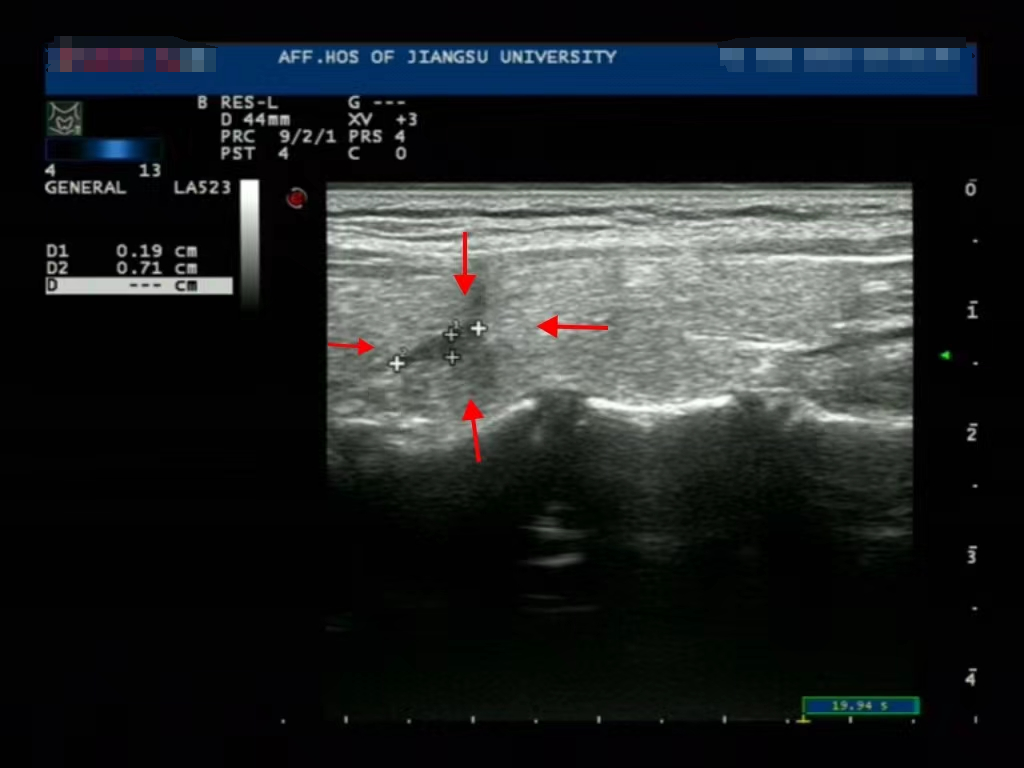

消融前

微波针是什么以“针”代“刀”,带你了解甲状腺结节微波消融术_https://www.jmylbn.com_新闻资讯_第11张

消融后3个月